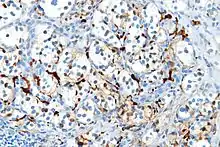

Порушення експресії S100 спостерігається при різноманітних злоякісний новоутвореннях, зокрема при меланомі, гістіоцитомі, парагангліомі, папілярному раку щитоподібної залози (протеїн S100A6).[2]